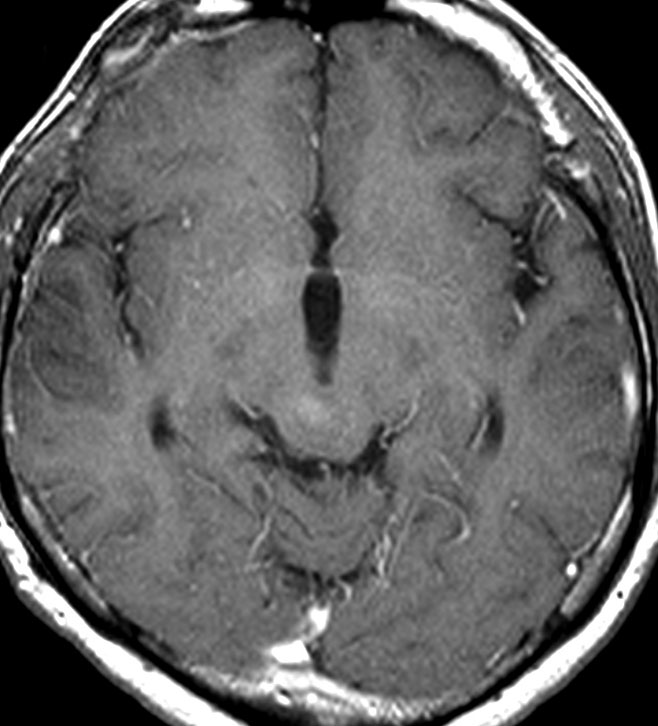

左はT1強調画像,右はFLAIR画像です。中脳視蓋が腫れて腫瘍がにじむように広がっているのがわかります。この腫瘍本体は15歳の時から21歳の時まで大きくなっていないので,中脳視蓋グリオーマ tectal gliomaの診断です。

T1強調ガドリニウム増強画像です。15歳の時は腫瘍の半分以上が強くガドリニウム増強されていましたが,この21歳の時の画像では,中心部やや右寄りに増強像が認められるだけです。この性質は,腫瘍が毛様細胞性星細胞腫であることを示しています。